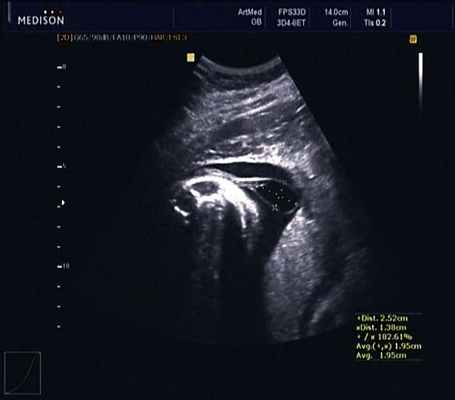

Ребенок от первой беременности после экстракорпорального оплодотворения. Беременность протекала с угрозой прерывания в I триместре, по поводу чего мать получала стационарное лечение. На сроке беременности 29 нед по данным УЗИ поставлен диагноз: врожденный порок развития - тератома, кистозное образование в области копчика (рис. 1). Родоразрешение на сроке гестации 39 нед путем кесарева сечения. Масса при рождении 3050 г, окружность головы 34 см, окружность груди 32 см, рост 50 см. Оценка по шкале Апгар 7/7.

В первые часы жизни ребенок доставлен в отделение реанимации и хирургии новорожденных НИИ детской хирургии НЦЗД РАМН. Проведена компьютерная томография (КТ) с внутривенным контрастированием и магнитно-резонансная томография (МРТ) пояснично-крестцового отдела позвоночника. Данные МРТ: в крестцовом отделе позвоночника имеется четыре позвонка на уровне позвонков SII-SIV, позвоночный канал деформирован, отсутствуют остистые отростки позвонков, имеется дефект канала на уровне позвонка SII, через который пролабируют оболочки спинного мозга. Размер грыжевого выпячивания 14×14×9 мм, содержимое - спинномозговая жидкость (рис. 2).